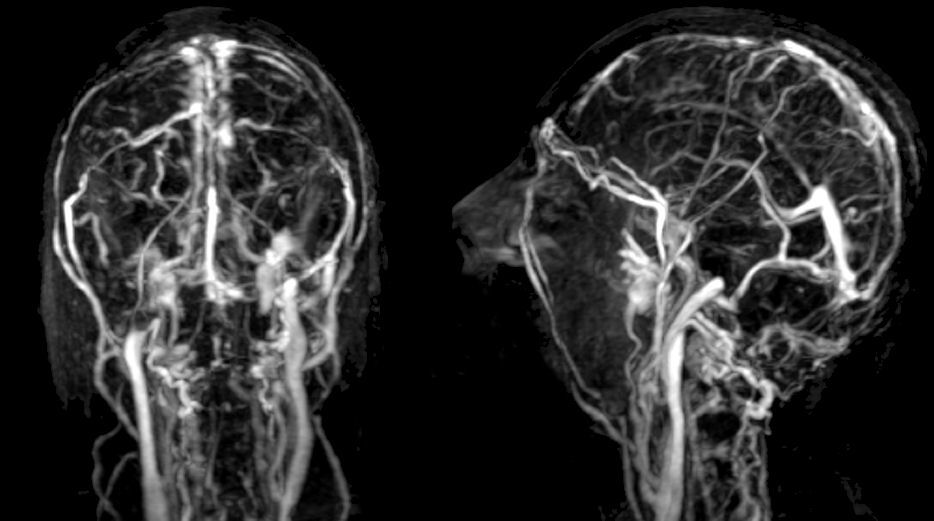

From animalia-life.club

Cavernous Sinus Thrombosis Mrv What Are The Symptoms Of Sinus Thrombosis This usually develops as a sharp pain located behind. Far and away, the most common symptom of venous sinus thrombosis is a headache. Cerebral venous sinus thrombosis (cvst) occurs when a blood clot forms in the brain’s venous sinuses. Swelling and bulging of the eye (s) and the. Symptoms of cavernous sinus thrombosis include: Cerebral venous sinus thrombosis symptoms depend. What Are The Symptoms Of Sinus Thrombosis.